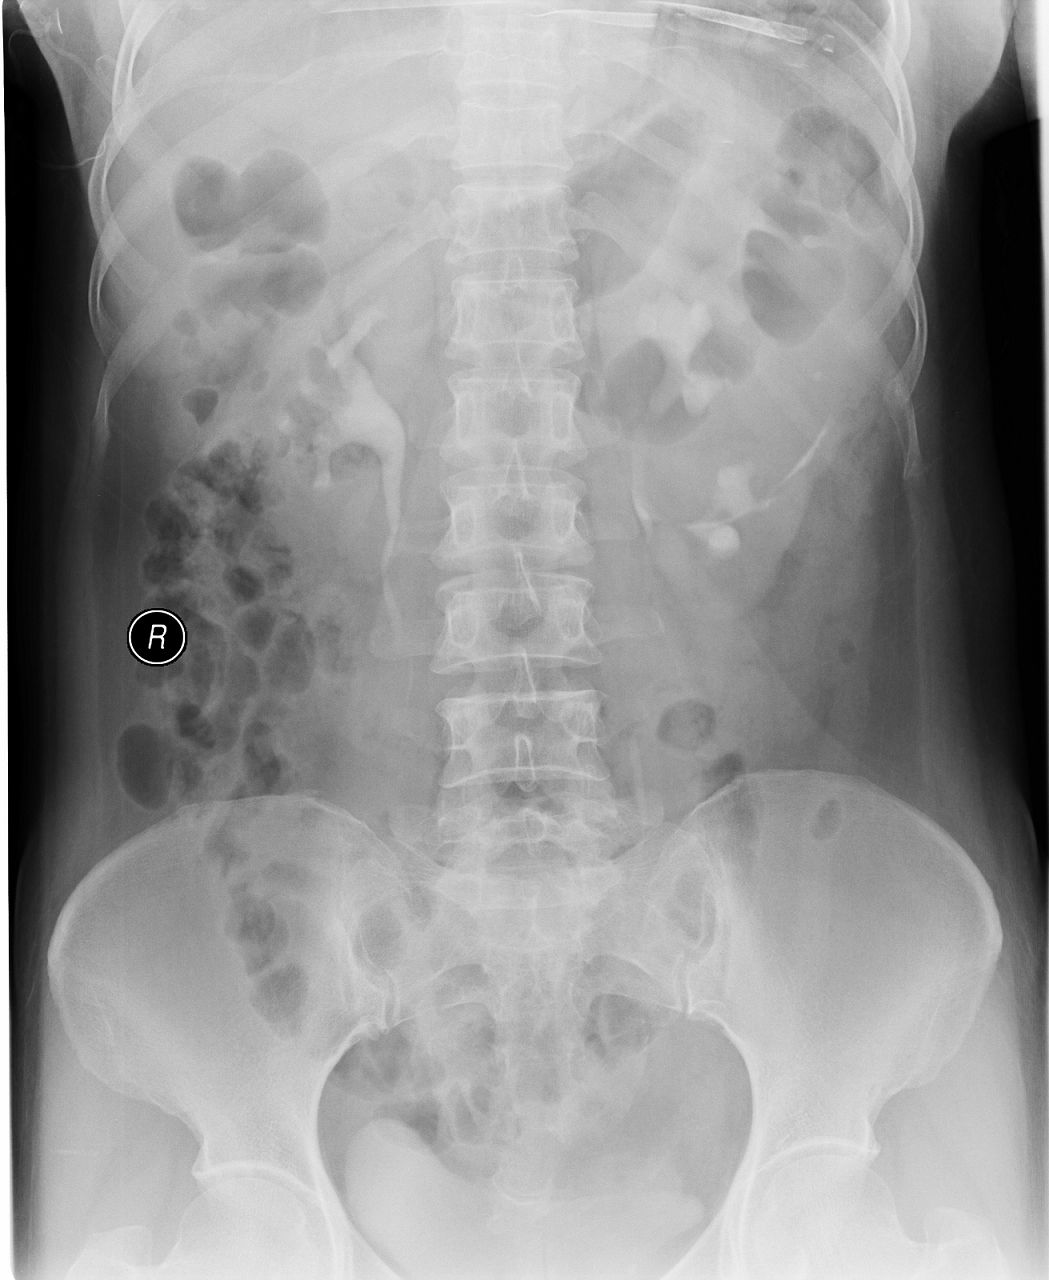

以下是引用杀毒软件在2008-7-27 17:11:00的发言:[br]肾盏分离,末端完整并少量积水-----暂支持楼主

以下是引用shiqingfa在2008-7-27 19:47:00的发言:[br]肾盏分离,末端完整并少量积水-----暂支持楼主